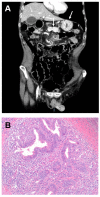

Small bowel carcinomas (SBC) are uncommon neoplasms, whose predisposing conditions include hereditary syndromes and immune-mediated intestinal disorders including coeliac disease (CD) and Crohn's disease (CrD). Although both CD-associated SBC (CD-SBC) and CrD-associated SBC (CrD-SBC) arise from an inflammatory background, they differ substantially in tumour cell phenotype, frequency of microsatellite instability and nuclear β-catenin expression, as well as in prognosis. For these patients, high tumour-infiltrating lymphocyte density and glandular/medullary histotype represent independent positive prognostic factors. Dysplasia adjacent to SBC is rare and characterized by intestinal phenotype and nuclear β-catenin in CD, while it is frequent and typified by gastro-pancreatobiliary marker expression and preserved membranous β-catenin in CrD. Recent evidence suggests that Epstein-Barr virus-positive dysplasia and SBC, albeit exceptional, do exist and are associated with CrD. In this review, we summarize the novel pathological and molecular insights of clinical and therapeutic interest to guide the care of CD-SBC and CrD-SBC.